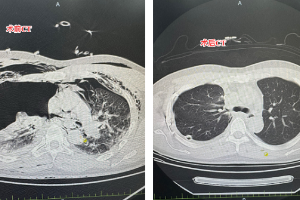

玉医胸外科特色专科门诊开诊

近日,玉溪市人民医院胸外科特色专科门诊开诊,包含肺癌早筛门诊及磨玻璃结节门诊。 肺癌早筛门诊 肺癌早筛门诊,是一项集临床医学、公共卫生、健康管理、信息技术于一体的系统工程。 目标人群(高危人群定义):年龄通常为50-74岁。 吸烟史:吸烟包年数≥30包年(例如:每天1包,吸30年;或每天2包,吸15年)。包括:当前吸烟者